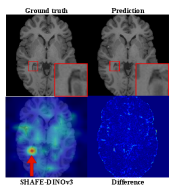

Smaller assigns exponentially greater weights, , to local and severe errors. Its patch-based design enables hallucination localization, with Fig. 7 showing SHAFE heatmaps accurately highlighting real failure regions.

We evaluated metrics on real restoration outputs by annotating 300 predictions from SwinIR [swinir], EDSR [edsr], and ESRGAN [ESRGAN]. SHAFE shows much stronger discrimination, improving AUC by 0.2 over traditional metrics (Table 3), aligning more closely with human judgment. Figure 7 shows that SHAFE provides distinctly better separation between images with and without hallucinations than LPIPS, demonstrating its robustness in real cases.

8.3 Localization

Fig. 10 presents the localization performance of SHAFE on both HalluGen samples and real restoration outputs generated by ESRGAN [ESRGAN] and SwinIR [swinir]. SHAFE consistently highlights hallucinated regions such as distorted lateral ventricles and disrupted sulcal boundaries, demonstrating its ability to detect both synthetic and naturally occurring failures. The resulting heatmaps are characteristically sparse, emphasizing localized deviations rather than diffuse artifacts. This sparsity further justifies the use of weighted softmax aggregation over uniform pooling, as it enables SHAFE to selectively amplify subtle but semantically meaningful hallucinated features.